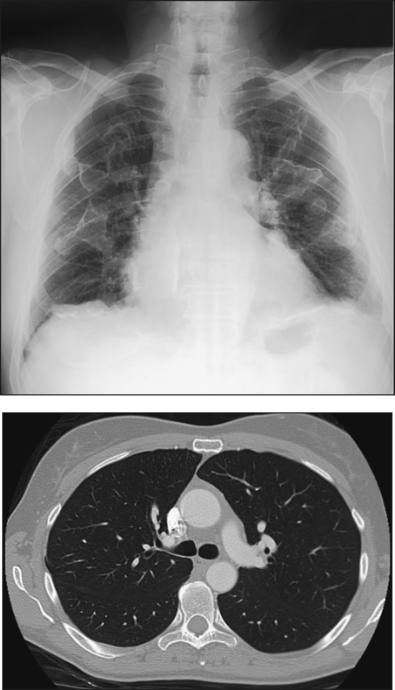

The lungs are the organs of respiration (Fig. 10-4). They are the mechanism for introducing oxygen into the blood and removing carbon dioxide from the blood. The lungs are composed of a light, spongy, highly elastic substance, the parenchyma, and they are covered by a layer of serous membrane. Each lung presents a rounded apex that reaches above the level of the clavicles into the root of the neck and a broad base that, resting on the obliquely placed diaphragm, reaches lower in back and at the sides than in front. The right lung is about 1 inch (2.5 cm) shorter than the left lung because of the large space occupied by the liver, and it is broader than the left lung because of the position of the heart. The lateral surface of each lung conforms with the shape of the chest wall. The inferior surface of the lung is concave, fitting over the diaphragm, and the lateral margins are thin. During respiration, the lungs move inferiorly for inspiration and superiorly for expiration (Fig. 10-5). During inspiration, the lateral margins descend into the deep recesses of the parietal pleura. In radiology, this recess is called the costophrenic angle (see Fig. 10-5, B). The mediastinal surface is concave with a depression, called the hilum, that accommodates the bronchi, pulmonary blood vessels, lymph vessels, and nerves. The inferior mediastinal surface of the left lung contains a concavity called the cardiac notch. This notch conforms to the shape of the heart.

Fig. 10-4 A, Three views of the lung. B, CT axial image through the thorax. Right and left lungs are shown in actual position within thorax and in relation to heart. Note nodule in right anterior lung (arrow). (B, Courtesy Siemens Medical Systems, Iselin, NJ.)